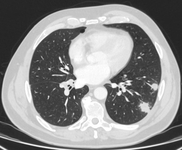

Computed tomography (CT) showing two areas (red circles) of mucoid impaction of the left upper lobe subsegmental bronchi, resulting in appearance that mimics a nodule

From the collection of Dr George Tsaknis, MD, PhD, FRCP(London), MRQA, MAcadMEd, PGCert; used with permission